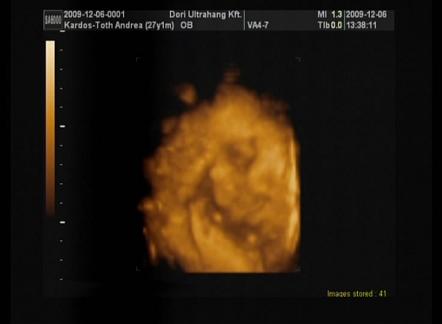

Remélem, mindent rendben talál ismét... lesz uh is, már nagyon várom!